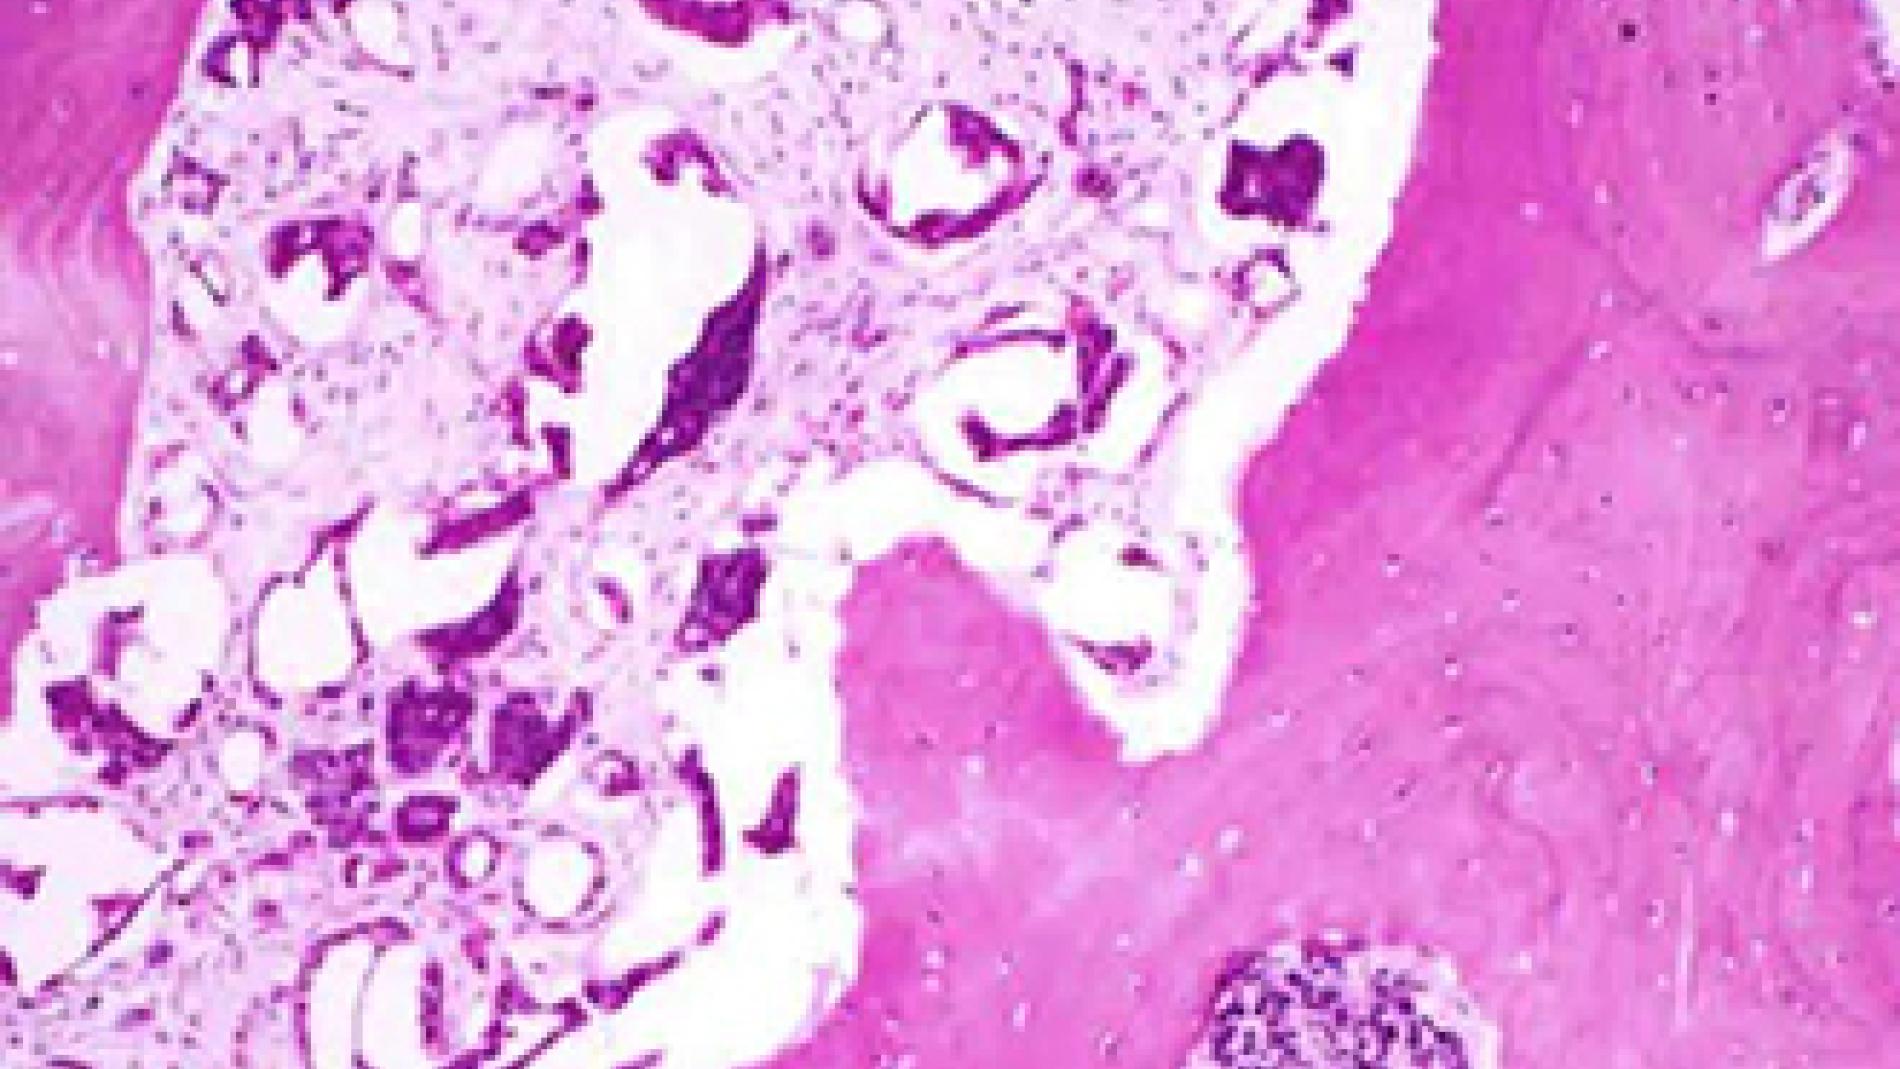

An international phase III study, conducted in 1717 patients with metastatic castration-resistant prostate cancer, demonstrates that the use of a new drug, called enzalutamide, before chemotherapy reduces the risk of death caused by the disease and slows down its progression. In this group of patients the tumor does not respond to the hormonal therapies aimed at reducing the male hormones (androgens) that make cancer cells grow. This study demonstrated that the administration of enzalutamide before chemotherapy in patients with metastasis who rarely had symptoms, blocks these hormones, so the start of the chemotherapy can start until 28 months later. Researchers from the Vall d’Hebron University Hospital and the Vall d’Hebron Institute of Oncology (VHIO) participated in this clinical trial, published in " "http://www.nejm.org/doi/full/10.1056/NEJMoa1405095?query=featured_home" The New England Journal of Medicine, that reduced by 81% the progression of the cancer, as compared with 14% among patients receiving placebo. Besides, the new drug is less toxic, with only side effects such as fatigue and hypertension.